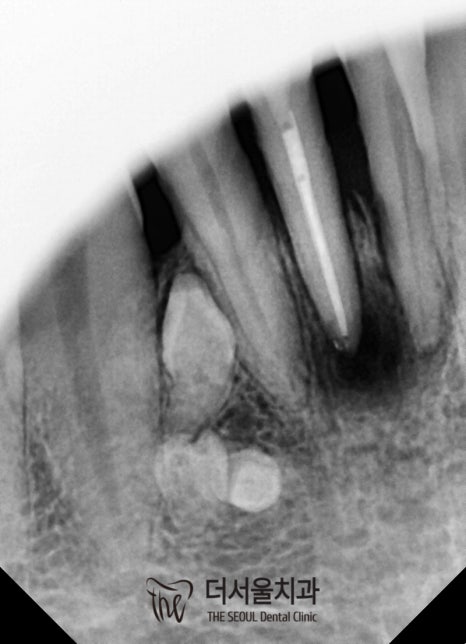

환자의 구강 내를 살펴보니

전체적으로 위생관리가 되지 않고 있었습니다.

『다량의 치석이

군데군데 쌓여있는 것이 관찰되시나요?』

치석은 치주 질환 및 충치 등

대표적인 구강질환의 주원인이죠.

현재 문제가 되는 곳 말고도

심한 치경부 마모증이 관찰이 되고 있었습니다.